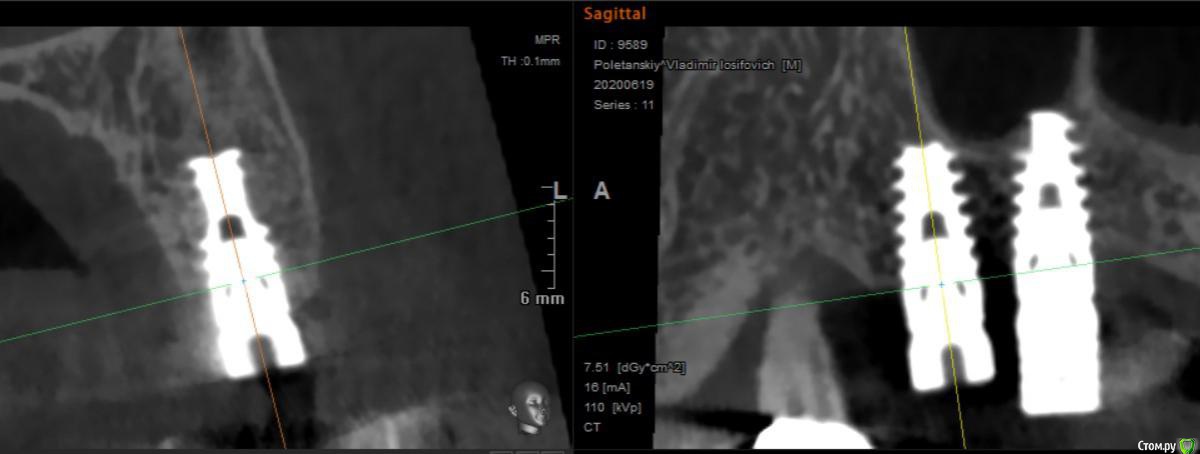

Foxtrot Опубликовано 8 июля, 2020 Поделиться Опубликовано 8 июля, 2020 Добрый день! Подскажите какая система. Пациент говорит: "какие-то израильские". По сайту whatimplantisthat.com - Alpha Bio Tec, хотелось бы еще услышать что тут скажут. Размер 4.2х10. Заранее спасибо! Ссылка на комментарий

red_butler Опубликовано 8 июля, 2020 Поделиться Опубликовано 8 июля, 2020 Да это альфа, легко удалите 4 Ссылка на комментарий